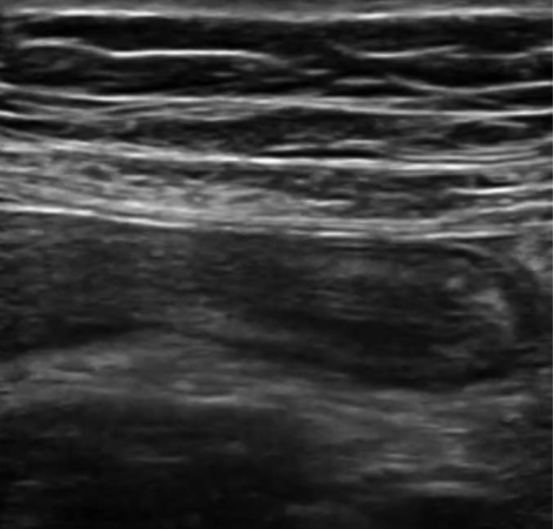

Characteristic sonographic findings include target sign in the short axis, blind-ended pouch in the long axis, lack of compressibility, diameter greater than 6 mm, wall thickness greater than 3 mm, appendicolith, and hypervascularity. Indirect findings suggestive of appendicitis include periappendiceal free fluid or abscess, hyperechoic mesenteric fat, enlarged mesenteric lymph nodes, increased peritoneal thickness, and signs of small bowel obstruction (SBO) [35] (Fig. 6).

Benefits of POCUS examination include lack of radiation exposure, lower costs, and ability to help prioritize radiology studies or expedite surgical consult. It may be particularly useful in centers where radiologist-performed US is not continually available. Visualizing the appendix is often limited by body habitus, pain, retrocecal location, and operator skill and experience. In addition, because a normal appendix is often difficult to visualize, this may be a more challenging POCUS study to learn [9, 34]. POCUS is a promising adjunct diagnostic tool, but it has not been extensively studied as a stand-alone test for appendicitis [34].